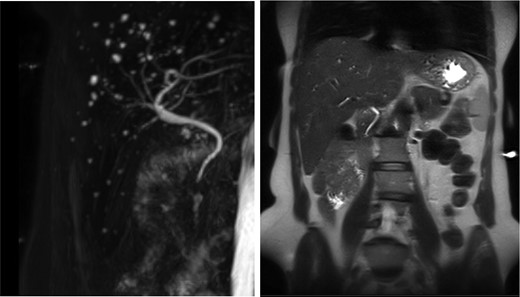

The patient’s symptoms markedly resolved in 3 days after admission; she was able to tolerate oral diet and was discharged with nearly normal biochemical levels. Repeated hepatobiliary ultrasonography showed no gallbladder with minimal common bile duct dilatation. Subsequent abdominal computed tomography (CT) and MRCP (Fig. 1) confirmed the diagnosis of congenital absence of gallbladder and cystic duct with multiple hepatic cysts.

Absence of the gallbladder and the cystic canal with the presence of multiple liver cysts.